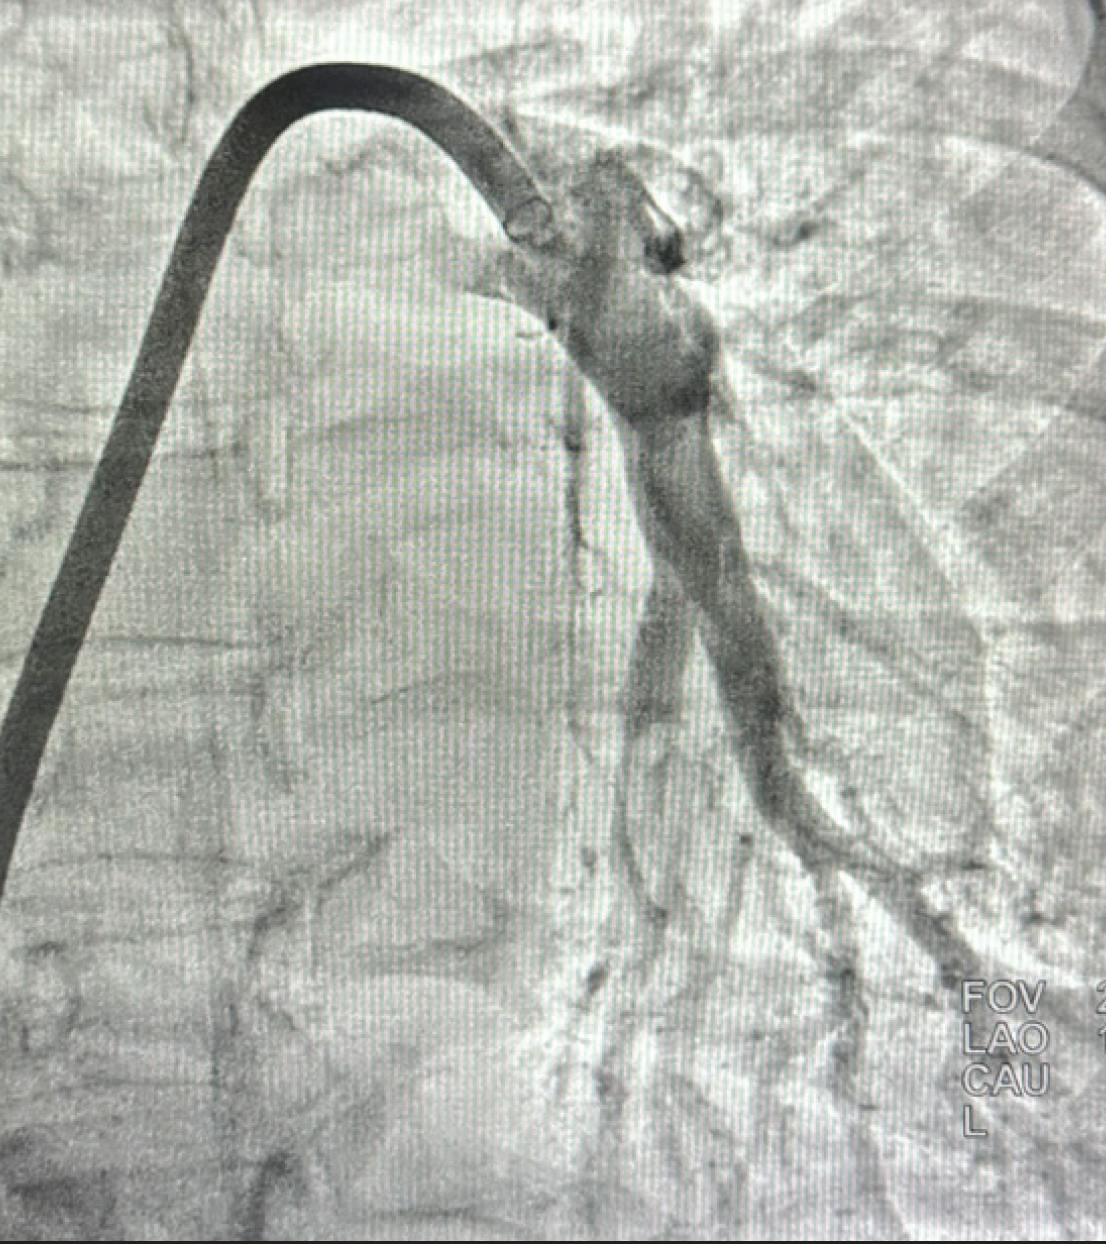

Pulmonary angiography demonstrated extensive thrombus in the left main PA and moderate distal thrombi in the right PA (Figure 3). The access site was preclosed with one Perclose ProGlide device (Abbott), and the sheath was upsized to a 16-F Gore DrySeal Flex introducer sheath (Gore & Associates) after serial dilation. A long J wire was advanced into the right PA, followed by introduction of the CAT16 aspiration catheter. After wire removal, CAVT was initiated, and multiple passes in the left PA extracted a significant amount of thrombus (Figure 4). Postthrombectomy angiography revealed marked reduction in clot burden (Figure 5). The total case time was 45 minutes, with a 3-minute device time using Lightning Flash 2.0. Final hemodynamics showed a PAP of 41/19 mm Hg (mean, 28 mm Hg). The 16-F sheath was removed, and hemostasis was achieved with one Perclose ProGlide.

Figure 3. Initial angiogram revealing extensive thrombus in the main PA.